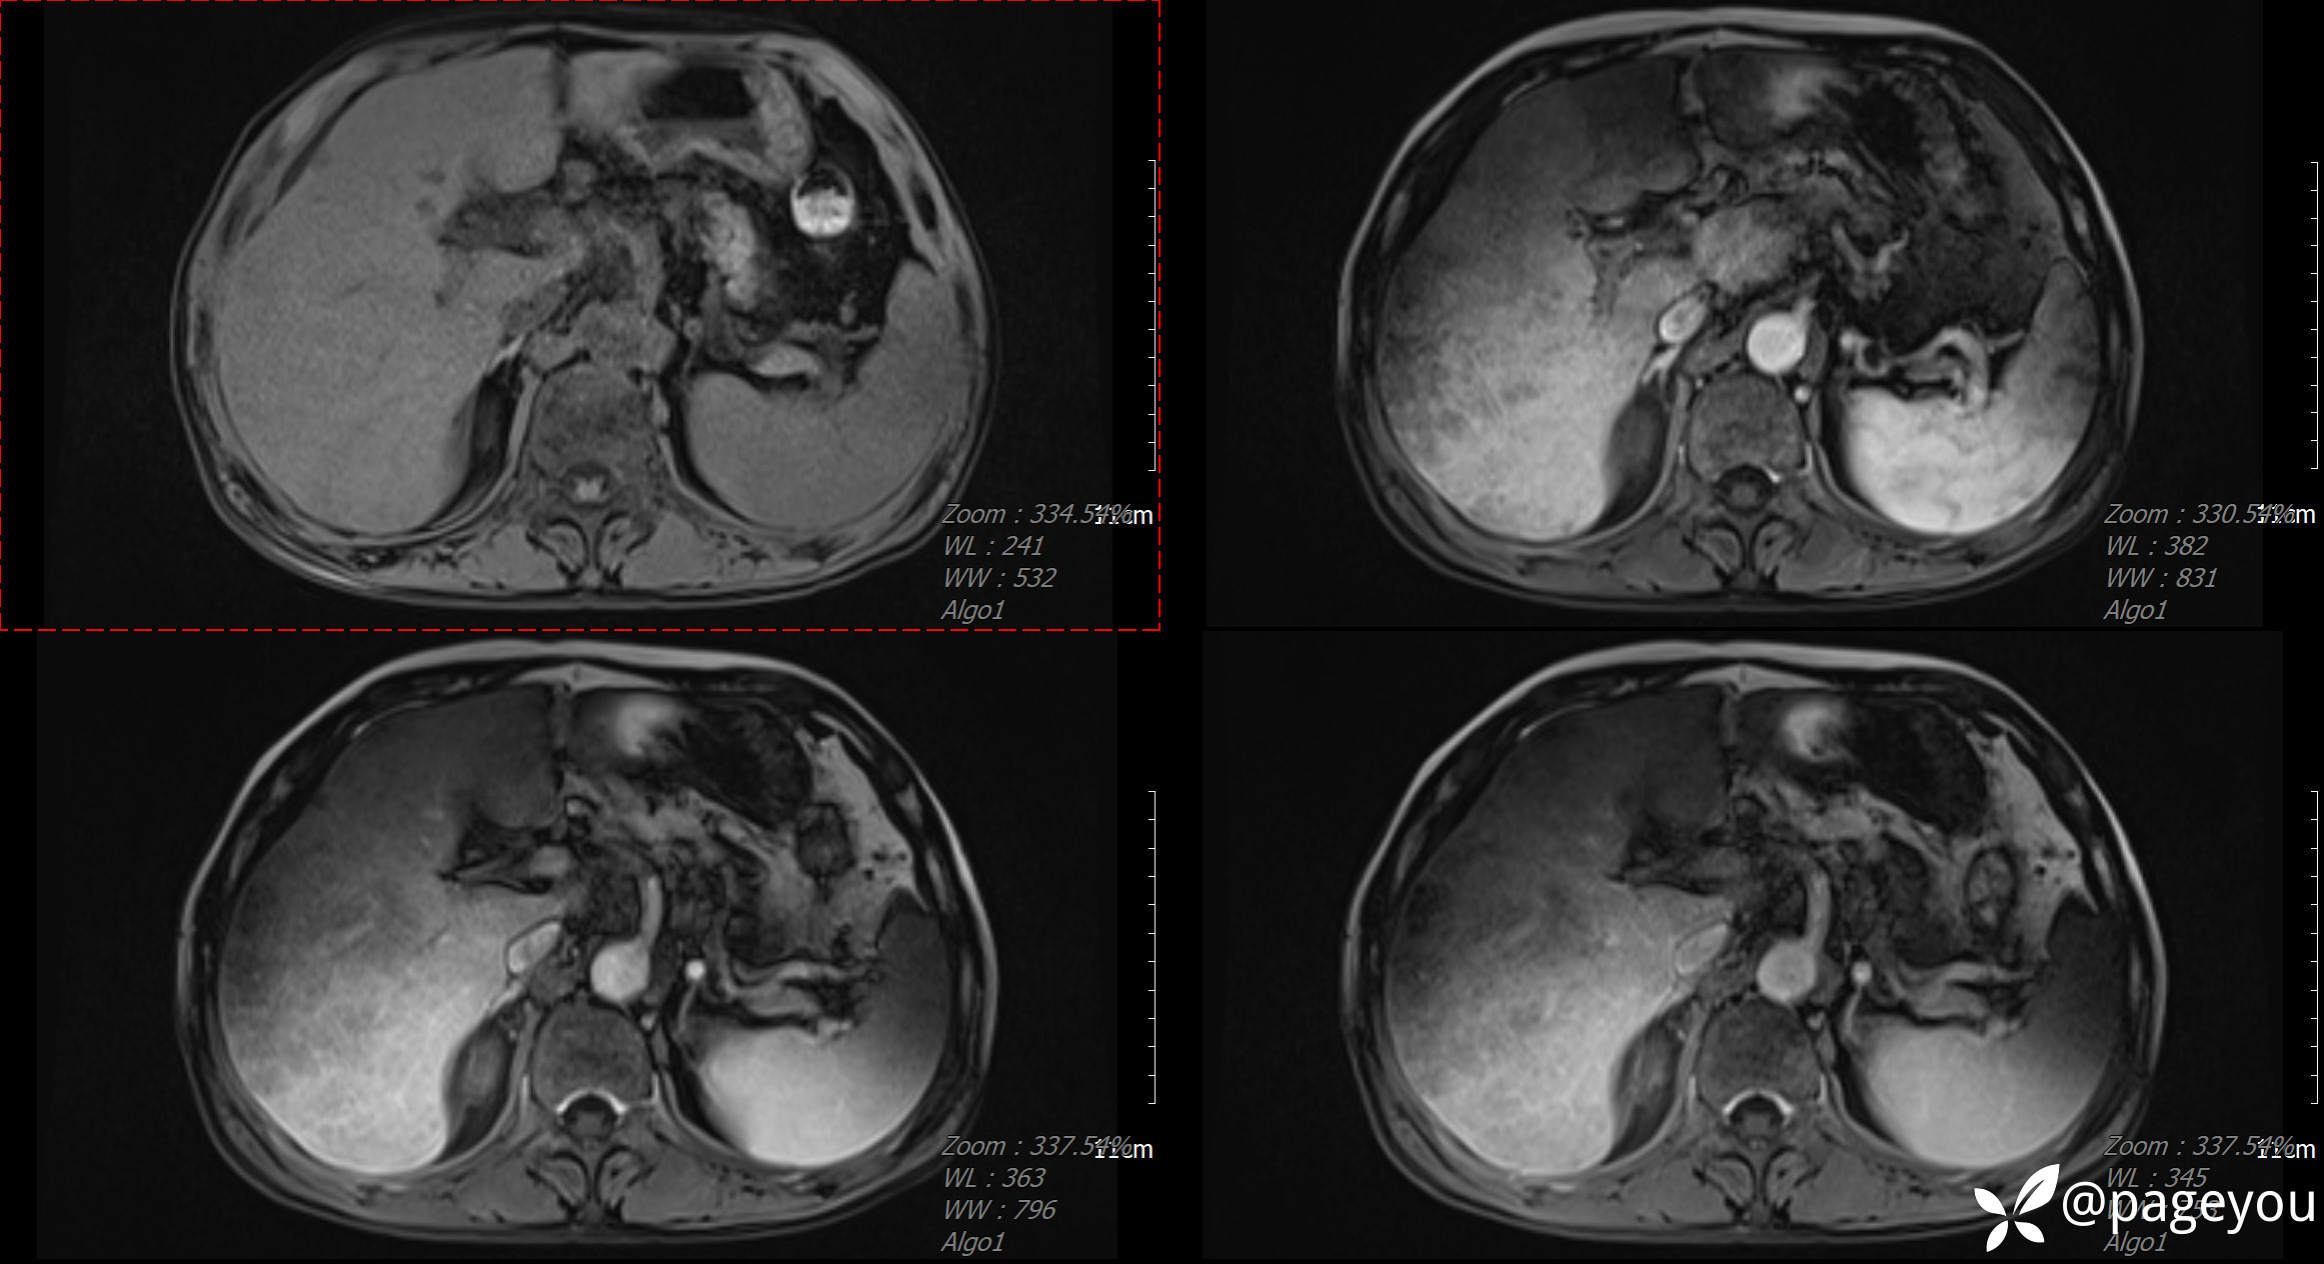

CT检查:

MRI检查: